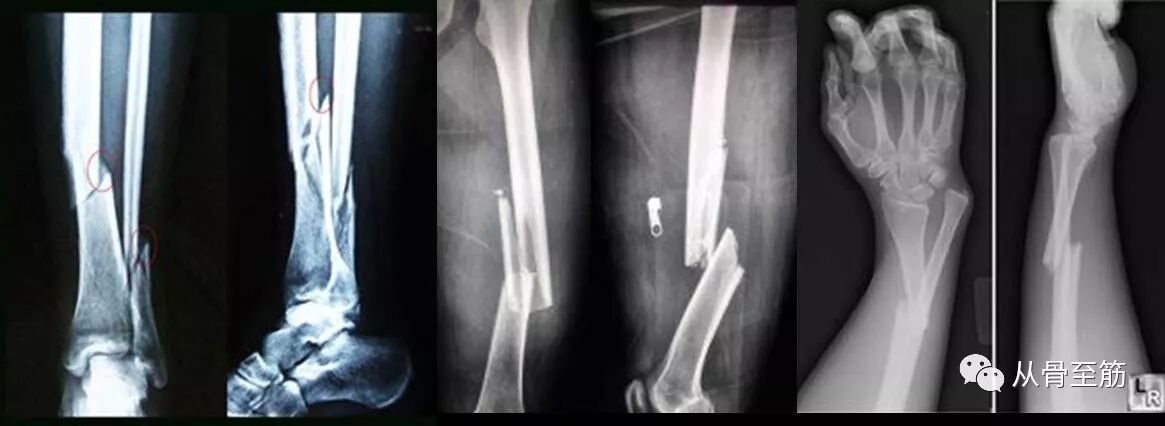

? ? ? ?外伤肿胀造成局部张力过大而引起水泡,医学上称之为“张力性水泡”。可以发生在身体任何部位,但以四肢居多,骨折周围部位最多。常见于小腿、前臂、膝、踝、肘、腕关节以及手足等处,大多在急性损伤后24-48小时出现。?

? ? 骨折发生时,局部软组织(特别是肌肉)也同时受损而出现肿胀,由于皮肤弹性有限,肿胀后皮肤变“紧”,局部压力增加,血管、淋巴管受压,血流回流阻力增加,加之血管受损,毛细血管通透性增加,液体渗出增多,骨折后出血使局部压力更高,渗液在表皮、真皮之间薄弱处积聚形成张力性水泡。骨折后,局部组织损伤程度不同,压力也不均,压力更高处会最先产生张力性水泡。

? ? 如果小血管损伤较重,出血明显会形成血泡。血泡表明皮肤全层损伤,提示伤情较重,局部软组织条件差。

? ? 水泡的出现提示软组织损伤较重。伤得越重,肿胀越重,水泡越多。这既增加了伤口感染的几率,又影响了手术的正常进行,延误骨折的治疗。有学者认为,水泡周围的皮肤尽量不做切口,因为皮肤坏死和感染的发生率很高。?